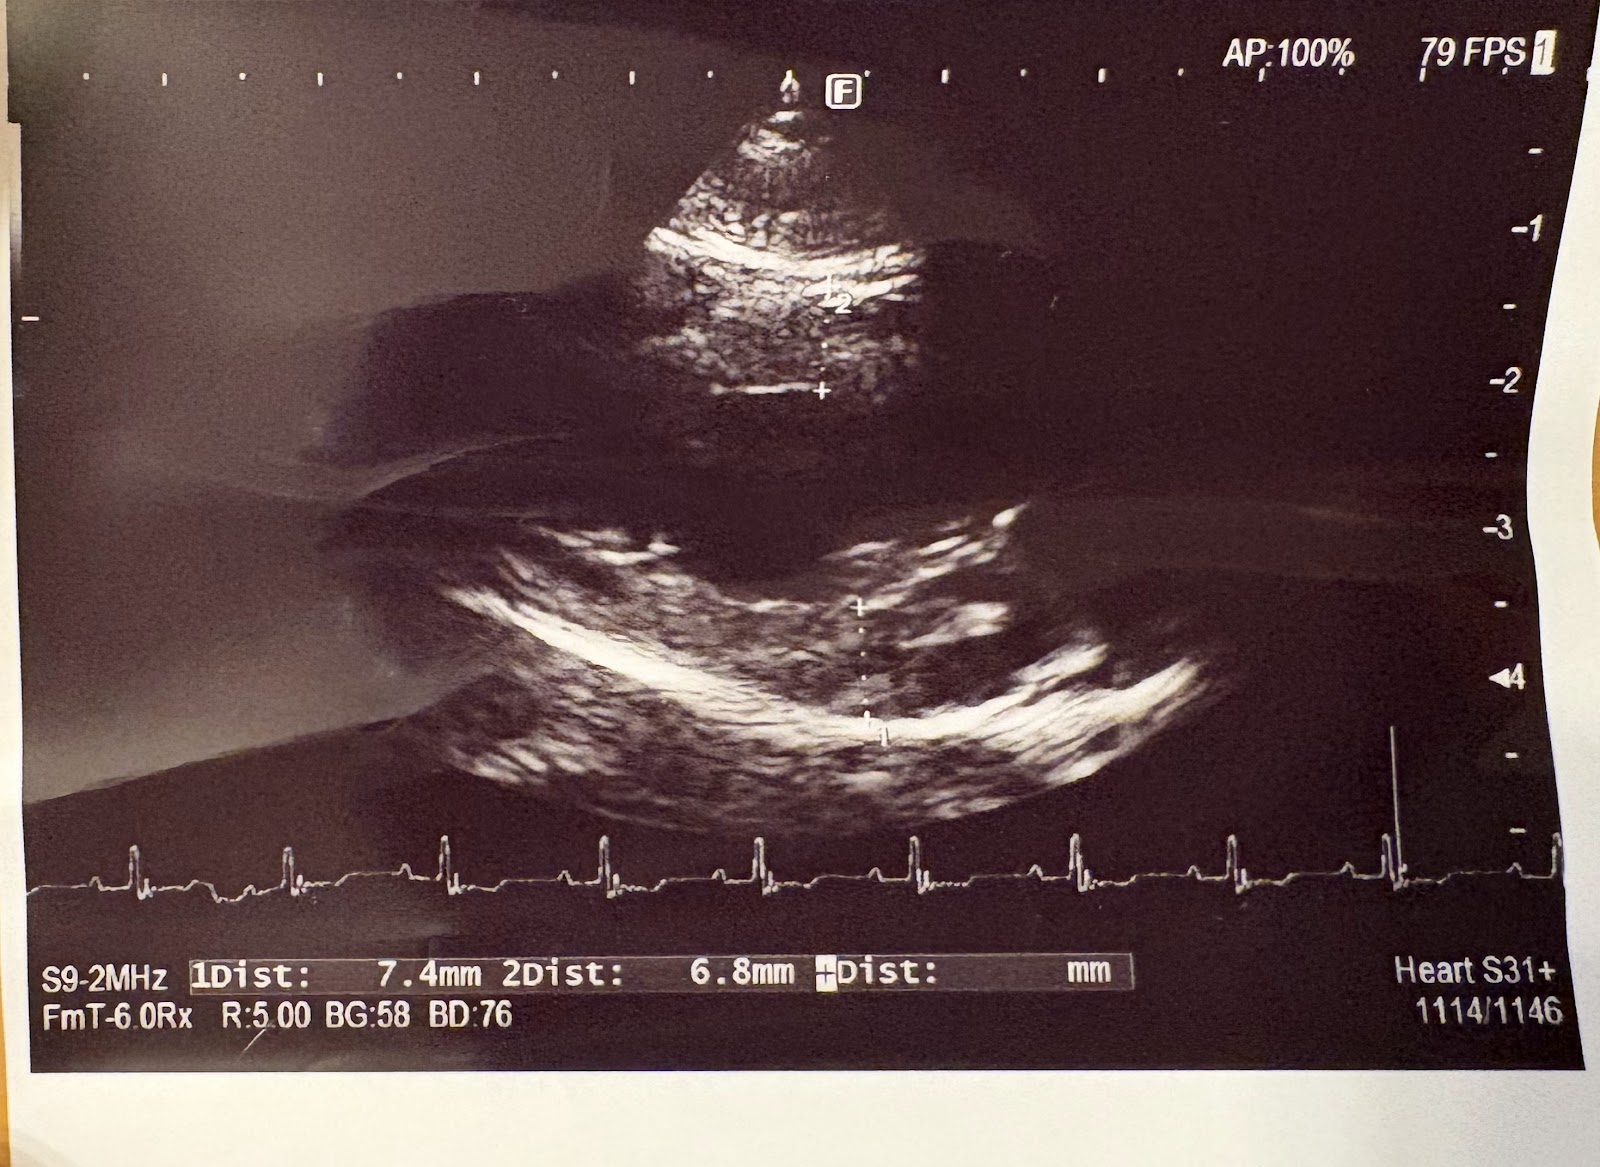

エコーです。

エコーでは肝臓は問題なさそうと言われました。

胆嚢に泥が溜まっているのでウルソは継続になりました。

腎臓は年齢相当だと。

胃腸は大丈夫そうだそうです。

膀胱にちらちらと石見たいのが見えるということでした。

心臓もちょっと壁が厚いと。。。